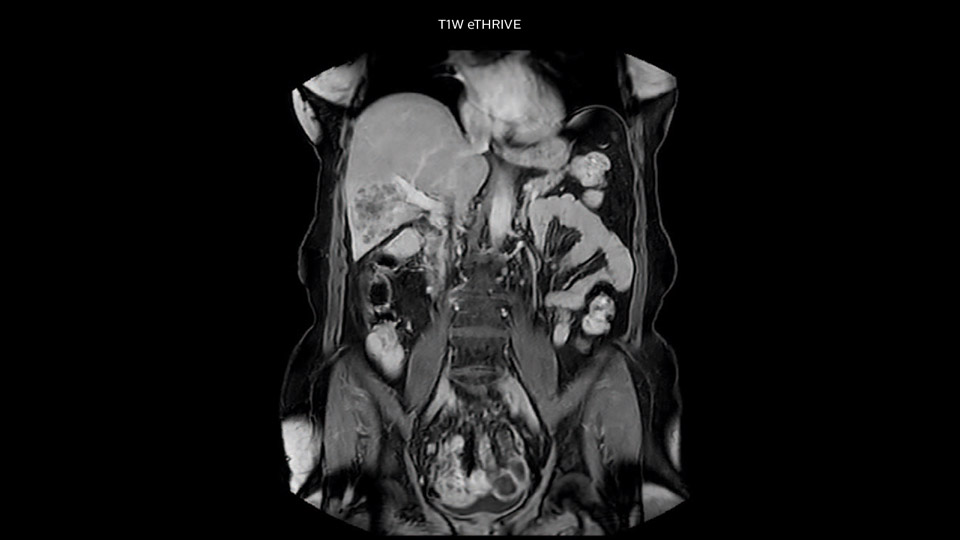

Comparison of liver MRI with and without MultiVane XD motion correction

In this example the image quality of the MultiVane XD images is evidently better than in the images without MultiVane XD. Ingenia 1.5T with dS Torso coil solution.

“We acquire one transversal high resolution T2-weighted sequence with 3 mm slice thickness, for example for pancreas or liver lesions. Then we also add a T2 fat suppressed MultiVane XD SPIR sequence. We perform these two routinely in our liver imaging. We use high dS SENSE factors to significantly shorten scan times to 2-4 minutes, which can improve our protocol; it’s a very robust scan.”

“We include mDIXON for the dynamic sequences because of the robust and homogeneous fat suppression we get with that. We had been using eTHRIVE, but we are now quite happy with mDIXON. Sometimes we use a medication to calm the bowels, to further improve the image quality.”